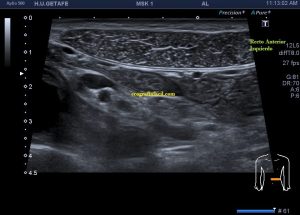

En este breve post te voy a presentar unas imágenes muy bonitas de una vesícula, en una paciente que acude a la cita de ecografía por sospecha de patología a ese nivel, con molestias anodinas e inespecíficas en el contexto de un estudio de su especialista de digestivo.

Observa las imágenes y luego te explico los hallazgos:

Cuando hice el corte longitudinal de la vesícula pude ver hasta tres patologías distintas, una adeomiomatosis (sin artefacto en cola de cometa), una litiasis vesicular y barro biliar, 2,3 y 4 respectivamente.

La adenomiomatosis, como un aumento de la ecogenicidad y el tamaño de la pared vesicular, la litiasis como una estructura hiperecogénica con sombra acústica posterior y el barro biliar, hiperecogénico rellenando toda la estructura ovoidea de la vesícula.

El cuello vesicular estaría afectado por la adenomiomatosis, el cuerpo por la litiasis y el barro ocuparía el fundas vesicular.

Para el estudio de la adenomiomatosis es obligado que el foco esté situado en la línea de interés, eso hará que las imágenes sean más nítidas y podamos estudiar dicha ecoarquitectura y su patología convenientemente.